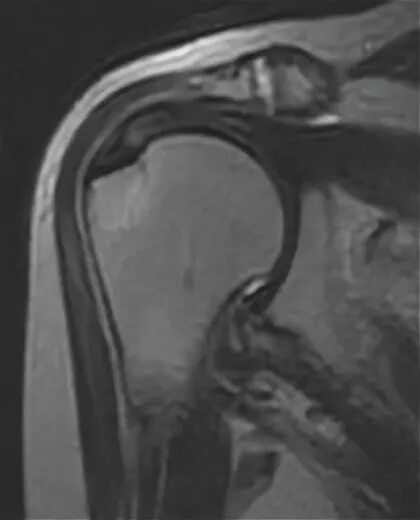

Мрт суставов пермь